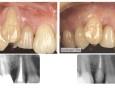

Pictures

Surgery